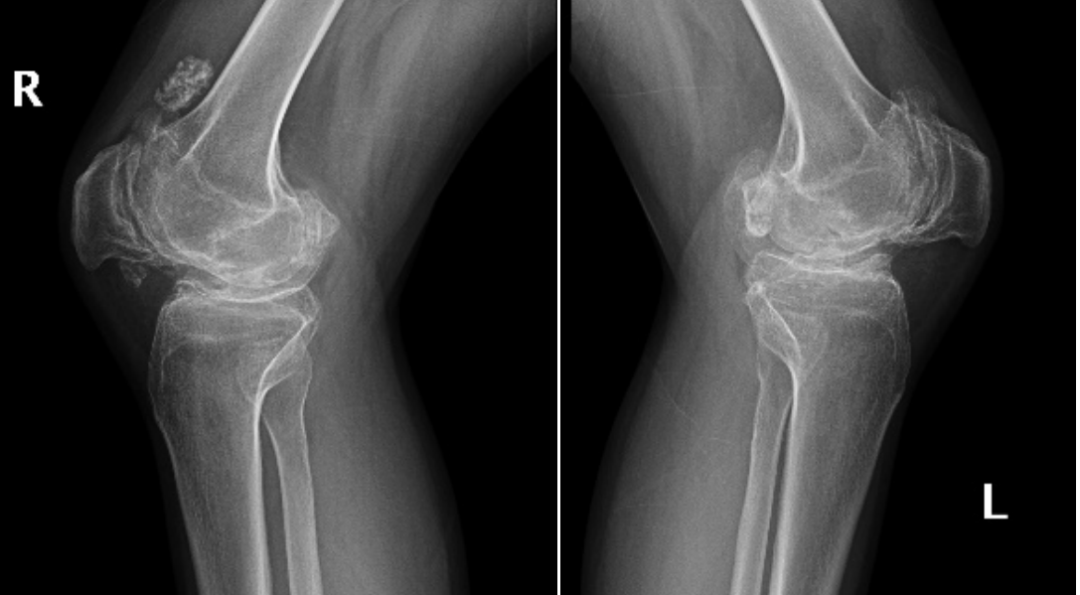

术前

一个月前,小许的膝关节出现僵硬症状,只能靠轮椅出行。「发病的时候非常非常痛苦,腿部膝盖和胯骨都特别疼、肿,三十出头的年龄就坐上了轮椅……」,这些让他失去理智的疼痛正是来源于强直性脊柱炎。

术后